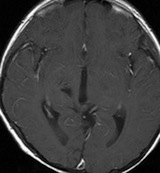

放射線治療13週目

右はガドリニウム増強です。ステロイドとグリセオールの点滴では制御できませんでした。悪性神経膠腫の病名で保険適応があるアバスチン(ベバシズマブ 10mg / kg)の投与を開始しました。

アバスチン投与後15日目

たった2週間で劇的な改善が見られました。失語症と片麻痺や認知機能も改善しました。